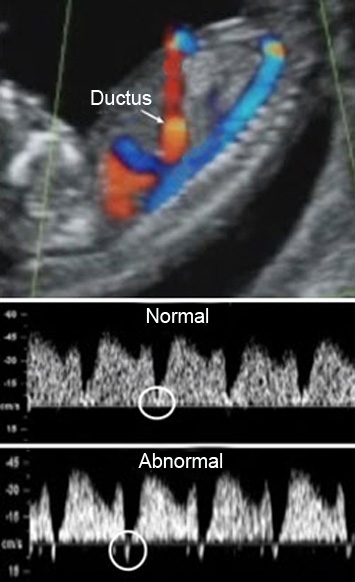

Ultrason Ölçümleri